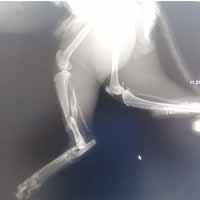

Yalıkavak veteriner kliniğimizde gerçekleştirdiğimiz ortopedik cerrahi uygulamalar:

Ortopedik cerrahi oldukça titizlik ve özen gerektiren cerrahi uygulamalardır. Diğer cerrahi disiplinlere nazaran asepsi ve antisepsi (sterilizasyon) konusunda ASLA hata kabul etmez. Eğer bu aşamada özensiz davranılırsa, postoperatif süreçte kemik dokunun iltihaplanmasına neden olup, kemiklerin kaynaması gecikmiş olur.

Bodrum Yalıkavak'lı pet sahiplerine özel: Ortopedik operasyon sonrası 1 ay boyunca ücretsiz kontrollerimizden yararlanabilirsiniz!